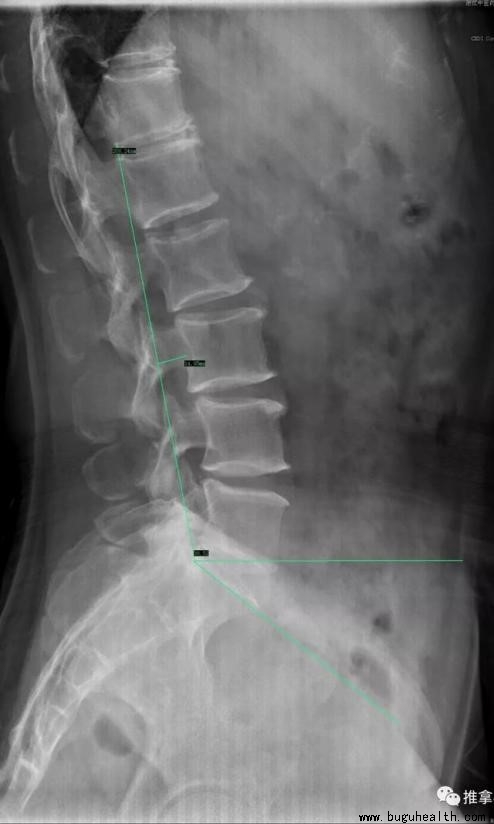

腰椎:Seze 法,即在 Χ 线侧位片上自T12椎体后下角至 S1后上角做一连线,腰椎各椎体后缘的弧形连线与此线形成一弓,弓顶点正常在 L3,弓顶点与弦垂线距离正常为18~22mm,大于22mm则为腰曲过大。

腰骶角:Ferguson测量法,即在Χ线侧位片上以骶骨上缘的切线与水平线做一夹角,即为腰骶角,研究表明正常值约为33.7°~49.1°,也就是如果腰骶角大于49.1°就可以说是腰骶角过大。